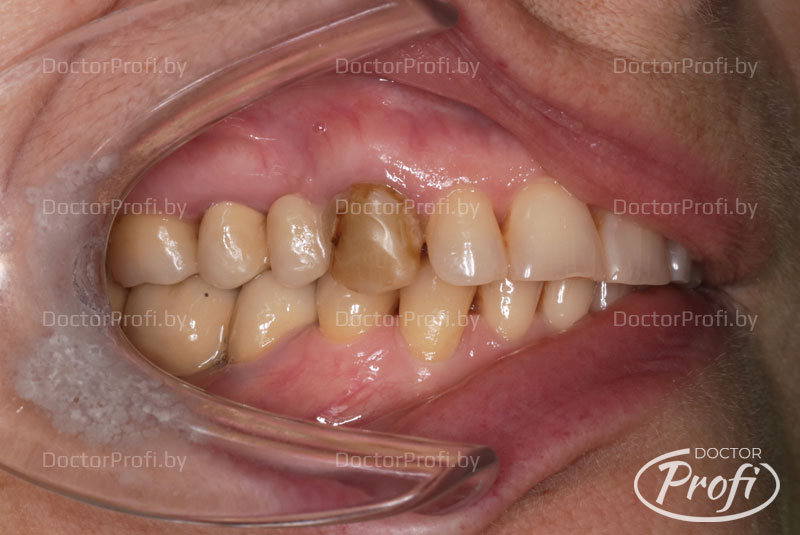

Пациент обратился в клинику «Доктор ПРОФИ» с жалобами на изменение цвета зуба 1.3, сколы керамической массы на искусственной коронке с консолью.

- Снята искусственная коронка с консолью 1.5

- Зуб 1.3 укреплен с помощью стекловолоконного штифта

- Установлен металлокерамический мостовидный протез на 3 единицы (1.5x1.3)

До